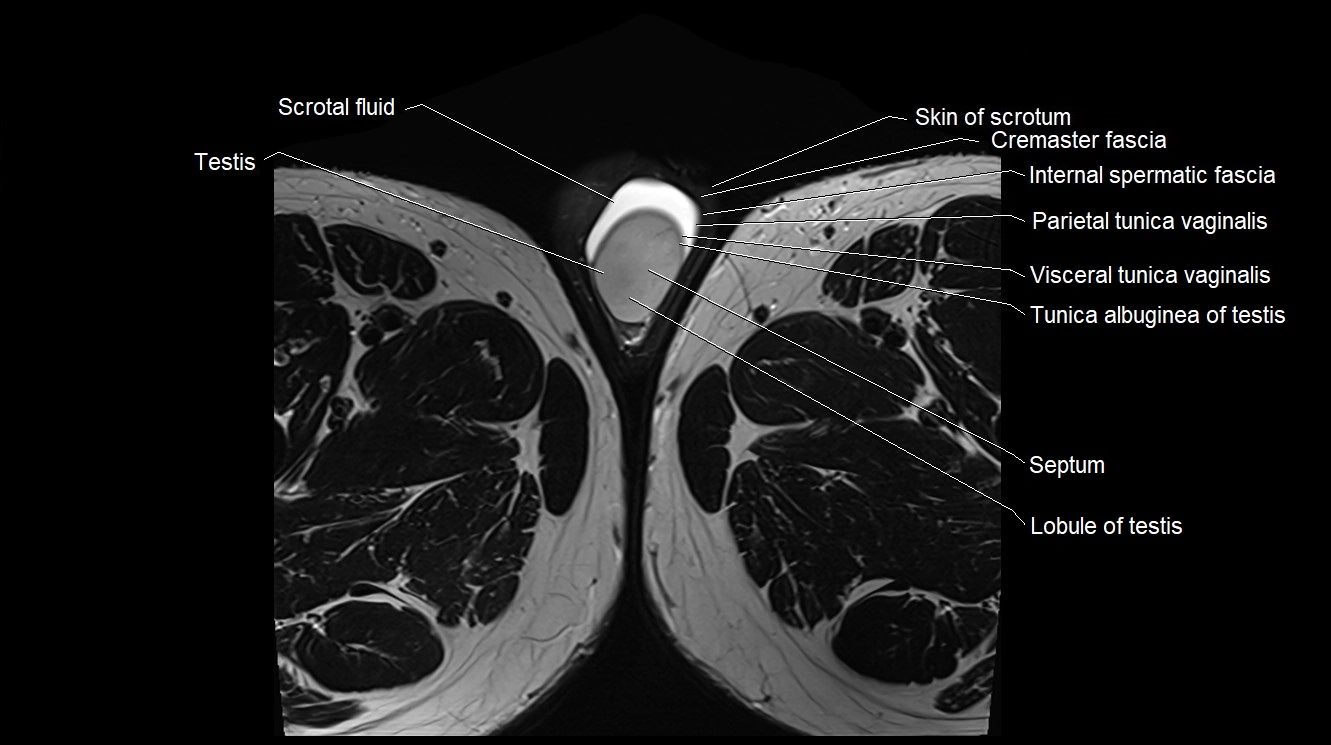

- Scrotal fluid

- Seminal vesicle

- Septum of scrotum

- Septum of testis

- Skin of scrotum

- Tunica albuginea of testis

- Visceral tunica vaginalis

- Parietal tunica vaginalis

- Lobule of testis

- Cremaster fascia

- Internal spermatic fascia